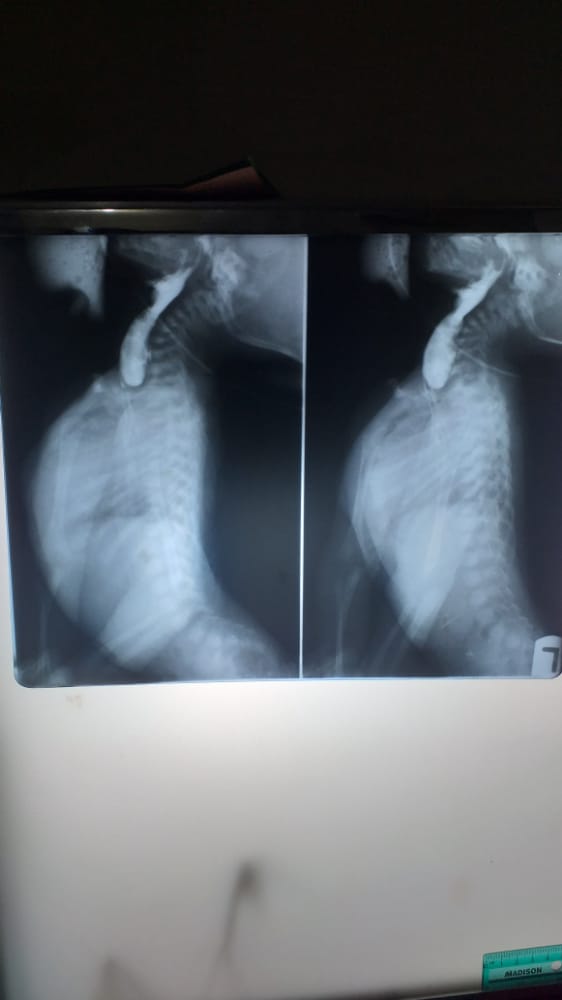

A contrast swallow (using low osmolar contrast medium: scanlux) was performed. This showed a blind ended esophagus with a pool of contrast medium (figures 3&4). The contrast was not demonstrated in the lung field. The distal esophagus and the stomach were also not contrast opacified. The vertebral spine showed normal appearances.

Figure 3: Lateral views of the contrast swallow demonstrating a proximal contrast filled pouch; the proximal esophageal atresia. Normal mediastinal shadow, pocket of lucency in the pelvic region. Normal bones of the thoracic cage and vertebral spine.